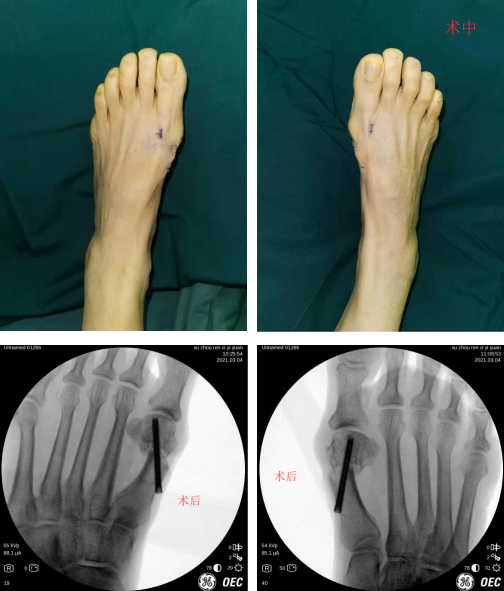

完善的术前检查后,石院长徐主任魏笛医生团队给患者进行了双足踇外翻截骨矫形内固定+拇收肌松解手术。术中,C型臂定位后,手术医生先后于右足及左足第1跖趾关节近端内侧做一1cm切口,采用低频超声骨刀微创截骨,向外侧轻推跖骨头端,以螺钉内固定,术中出血仅20毫升。老人及家属对手术效果很满意。